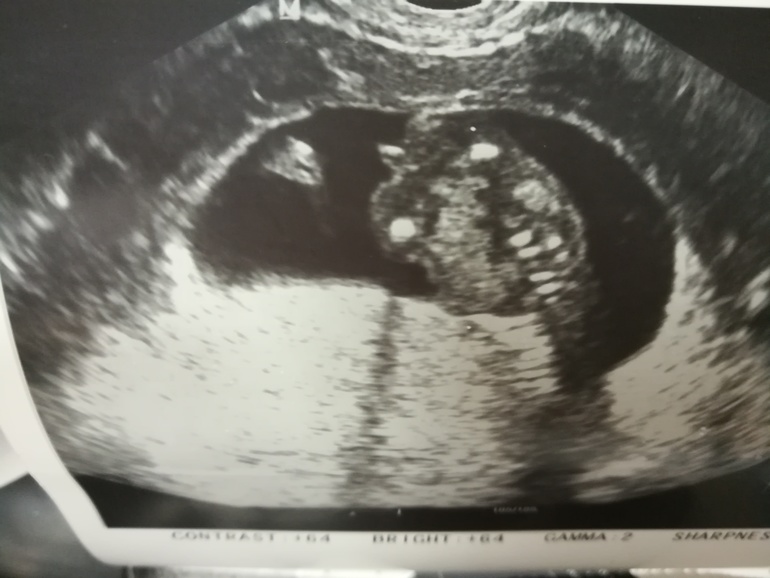

Наш первый скрининг 😍

Отдам даром детские товары/аптека.Сегодня прошёл мой первый скрининг. Одного малыша сразу увидели . Мальчик ) баловный, руками машет ногами дрыгает ! Просто звезда ! Смешной до ужаса . Все показал , все ему измерили . А вот второй , или вторая на тот момент мы ещё не знали , спрятался . Просто отвернулся спиной . И лежал в позе эмбриона . Я и кашляла , и стучала врач ему а он не в какую . Заставили меня съесть зачем то конфету , и походить в коридоре . И вот я снова легла , а этот второй развернулся полубоком. Врач говорит девочка . Хотя сомневаюсь . И тут первый малыш повернулся ко второму и давай ему через стенку стучать , мол давай повернись уже . Мы так смеялись . Вообщем с горем пополам наш второй ребёнок показал нам что он мальчик , и общаться он пока не настроен 😀 пальчики , носик , все на месте . Муж счастлив. Мы их уже очень любим . Как врач сказала папина футбольная команда . Страшно кончено мне , будут одни мужики )))) будут на голове ходить . Ну зато я буду их любимая Мамочка . Кровь сдала , жду ещё кровь пережеваю ... ну и из плохого , белок в моче подтвердился . Пойду в среду на узи почек . А в целом я счастлива . Боюсь в основном за малышей . Я пережеву любые боли, лишь бы сыночки были здоровы . Наверно рассуждаю как и любая мама. Хочу чтобы этот день запомнился , поэтому оставлю это в своём дневнике .